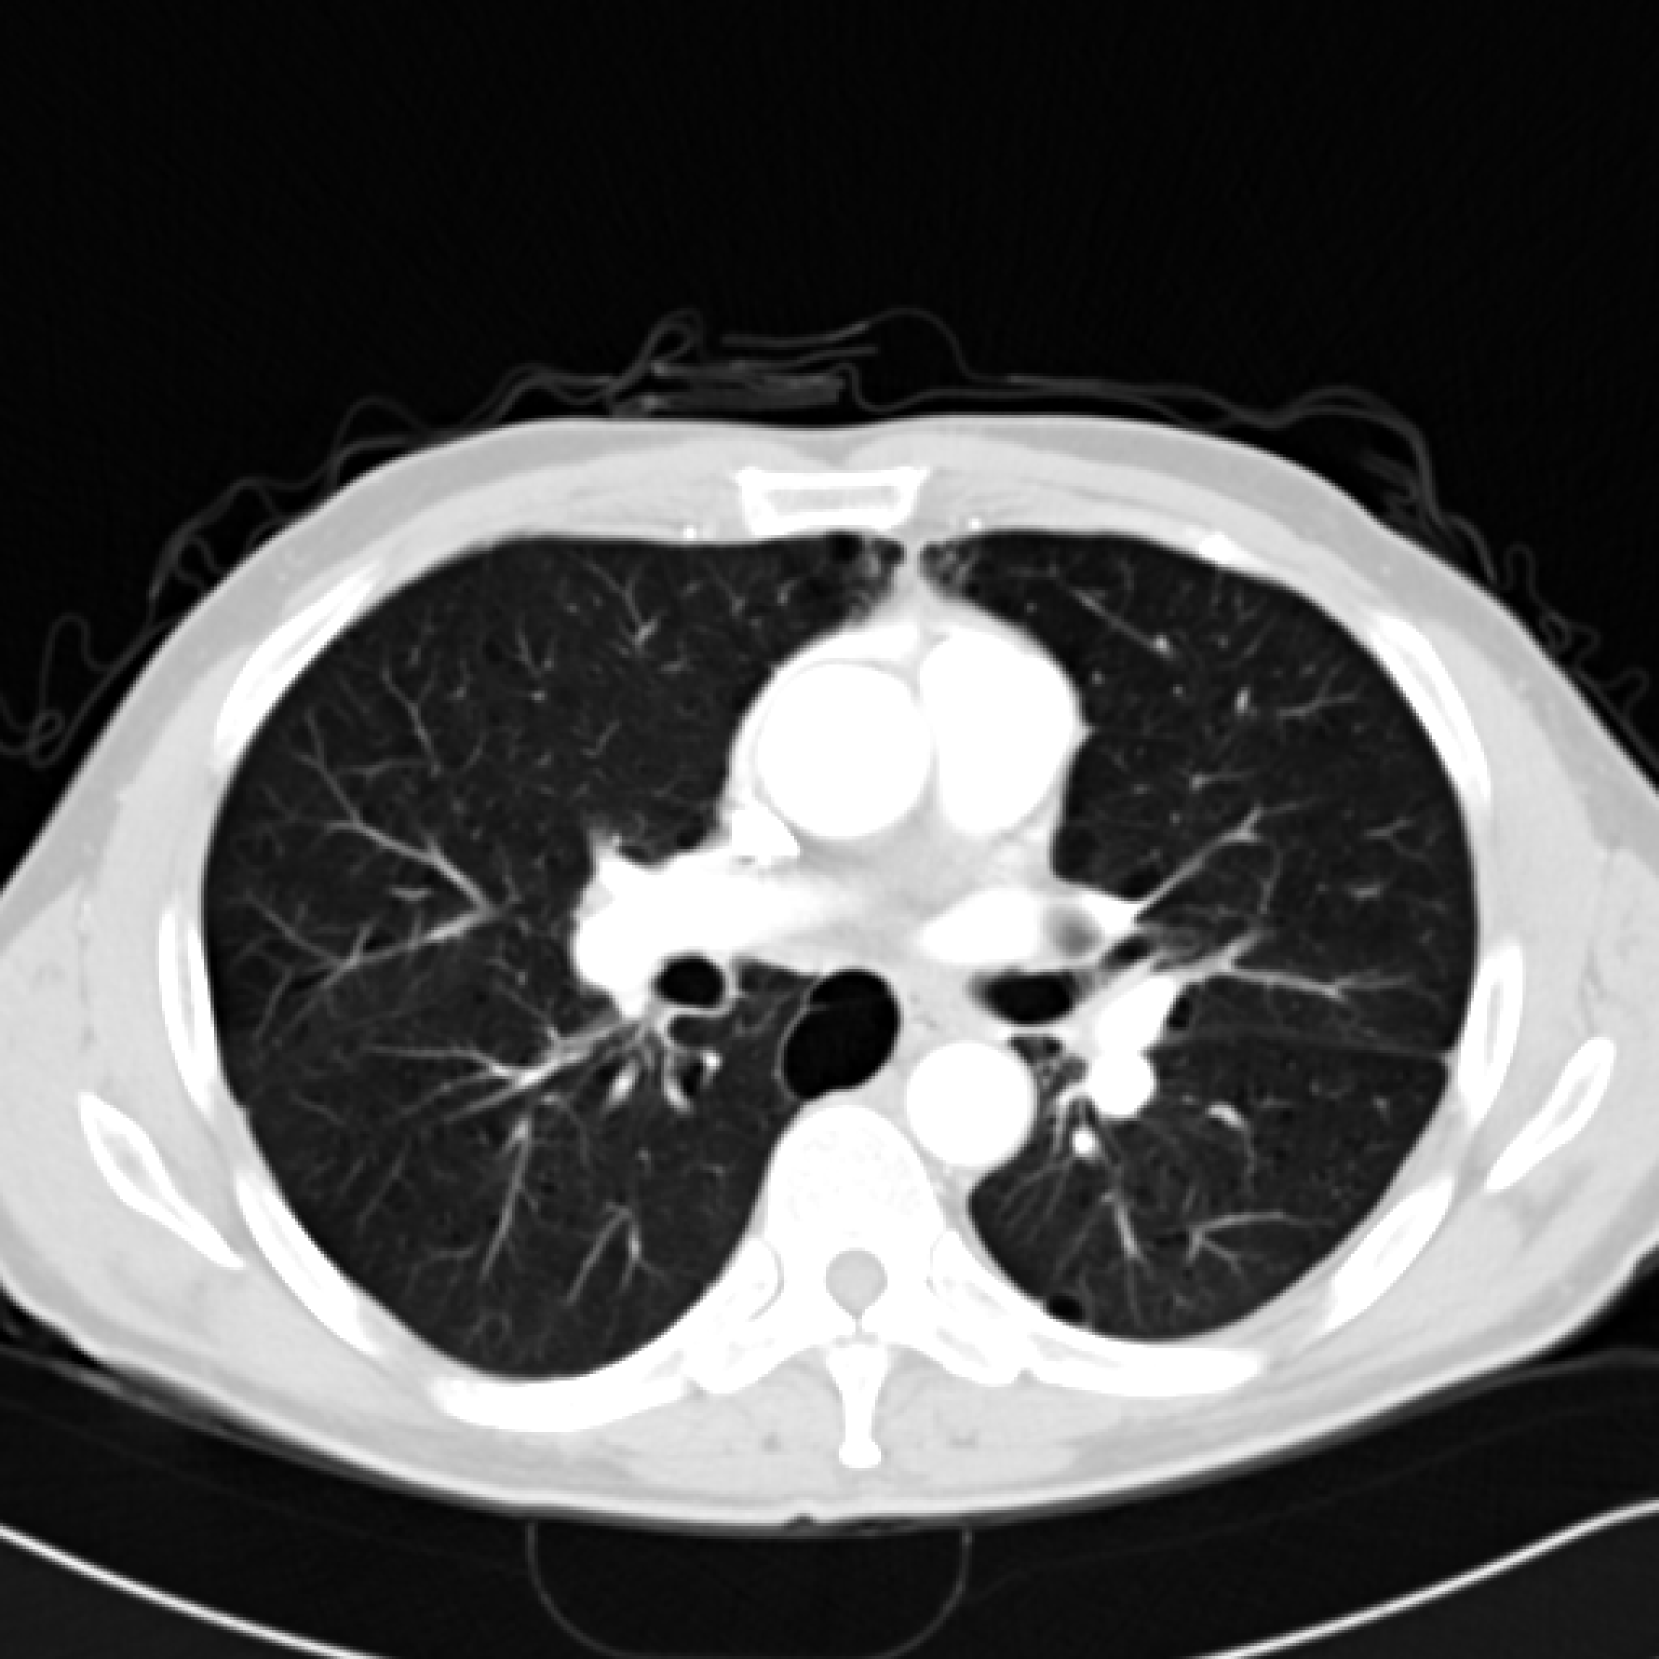

Figure 4: Experiments on computed tomography reconstruction with various INR architectures. We report average PSNR and standard error across five random trials.

5.1 Computed Tomography(CT) Reconstruction

In this experiment we simulated CT reconstruction by taking 100100100100 equally spaced CT measurements of a 326×435326435326\times 435326 × 435 chest X-ray image (Clark et al., 2013). Figure 4 shows the results compared to other INR architectures showing that our BW-ReLU neural networks perform just as well and perhaps slightly better than conventional INR architectures. Full experiment details can be found in Section D.1.